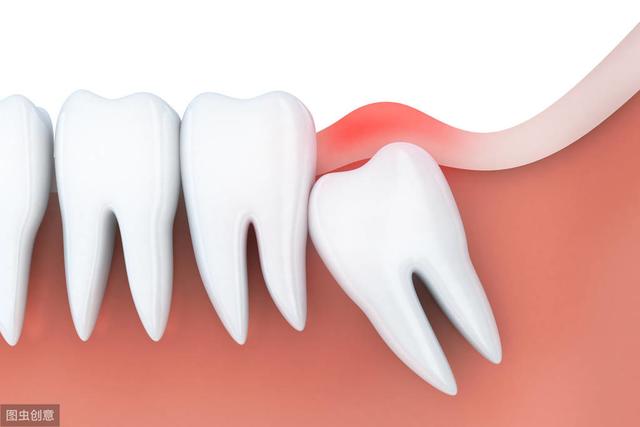

阻生智齿是智齿中最常见的类型,通常埋在牙槽骨内。阻生牙牙冠周围的牙龈常常会发炎,疼痛,严重时脸颊可以肿胀,张口困难,甚至全身发热,颌下淋巴结肿大,症状和严重的感冒发烧非常相似。

阻生牙常常还会引起邻牙龋坏松动,牙槽骨吸收等症状。如果感觉到疼痛或诊断会有病灶发生时,甚至邻牙也需要拔除。智齿的阻生有很多种位置,最常见的就是下颌智齿阻生在下颌神经管附近,呈水平方向,抵住第二磨牙远中部分。